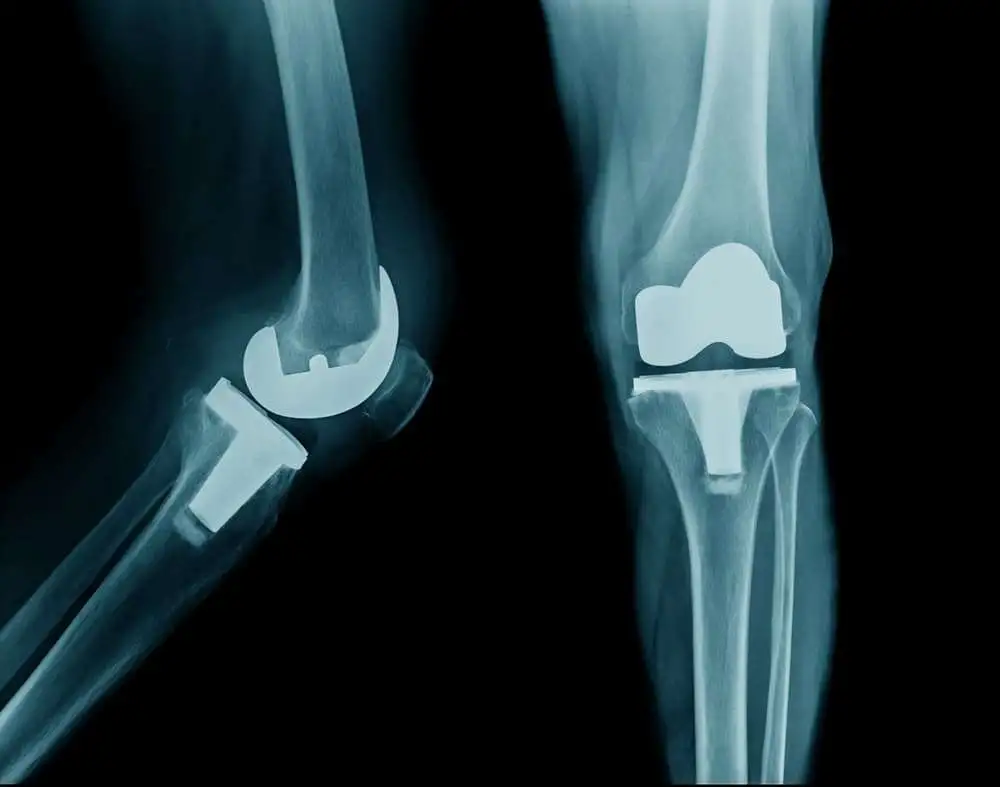

Изучение снимков коленных суставов показало сужение медиальной тибиофеморальной суставной щели и формирование остеофита. Лабораторные анализы, включая анализ крови (фактор РА/CRP) и другие биохимические анализы, оказались в норме. Уровень мочевой кислоты в сыворотке был в пределах нормы, что свидетельствовало об отсутствии подагры. Уровень сывороточного кальция был на нижнем пределе нормы (90 мг/л).

Рентгенологические результаты после одного года показали улучшенные уровни остеоартрита (I степень), имевшего ранее показатель IV степени, и увеличенный объем движений (115 градусов).